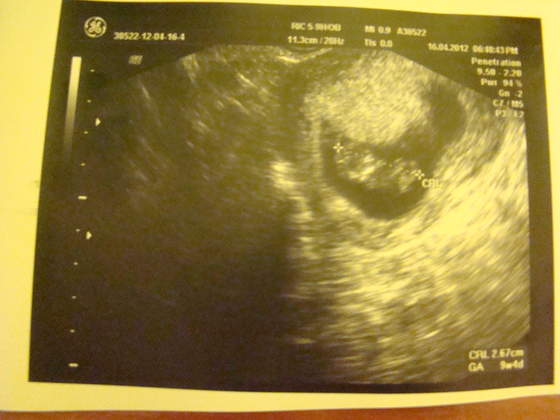

Już się nie mogę doczekać na relację z kolacji (chodzi o Juleczkę;-)) i na fotkę Fasola!!!! Bo to chyba chłopak będzie